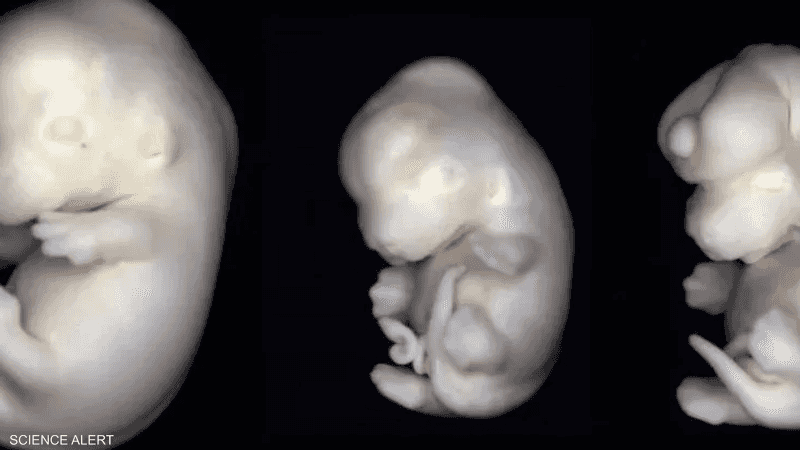

كشفت دراسة حديثة أن مواد كيميائية موجودة في بعض الأدوات المنزلية والملابس التي تستخدم يوميا قد تعيق نمو وجه الأجنة وقد تسبب لهم تشوهات.

يؤثر "بي إف دي إيه" على حمض الريتينويك، المعروف أيضا بفيتامين A، وهو عنصر أساسي في تشكيل وجه الجنين خلال المراحل المبكرة من الحمل. إذ يمنع هذا المركب إنزيما يعرف باسم "سي واي بي 26 إيه 1"، المسؤول عن تنظيم مستويات حمض الريتينويك، كما يقلل من إنتاجه.

ومن أكثر هذه التأثيرات شيوعا: صغر حجم العينين وتكون غير طبيعي للفك.

وأوضحت ميلانوفا أن حمض الريتينويك يتحكم في مئات الجينات المسؤولة عن تكوين وجه الجنين وعينيه وجهازه العصبي.

يبدأ تطور ملامح الوجه في الثلث الأول من الحمل ويستمر طوال فترة الحمل، ما يعني ضرورة الحذر منذ مرحلة التخطيط للحمل وحتى الولادة.

وحذرت ميلانوفا من أن الفترة الأكثر خطورة تمتد بين الأسبوع الرابع والعاشر من الحمل، حيث تتشكل ملامح الوجه والفك والعينين.

وأضافت أن الجنين لا يستطيع تنظيم مستويات حمض الريتينويك بنفسه، بل يعتمد كليًا على جسم الأم، ما يجعل أي اضطراب كيميائي خلال هذه الفترة خطيرا للغاية.